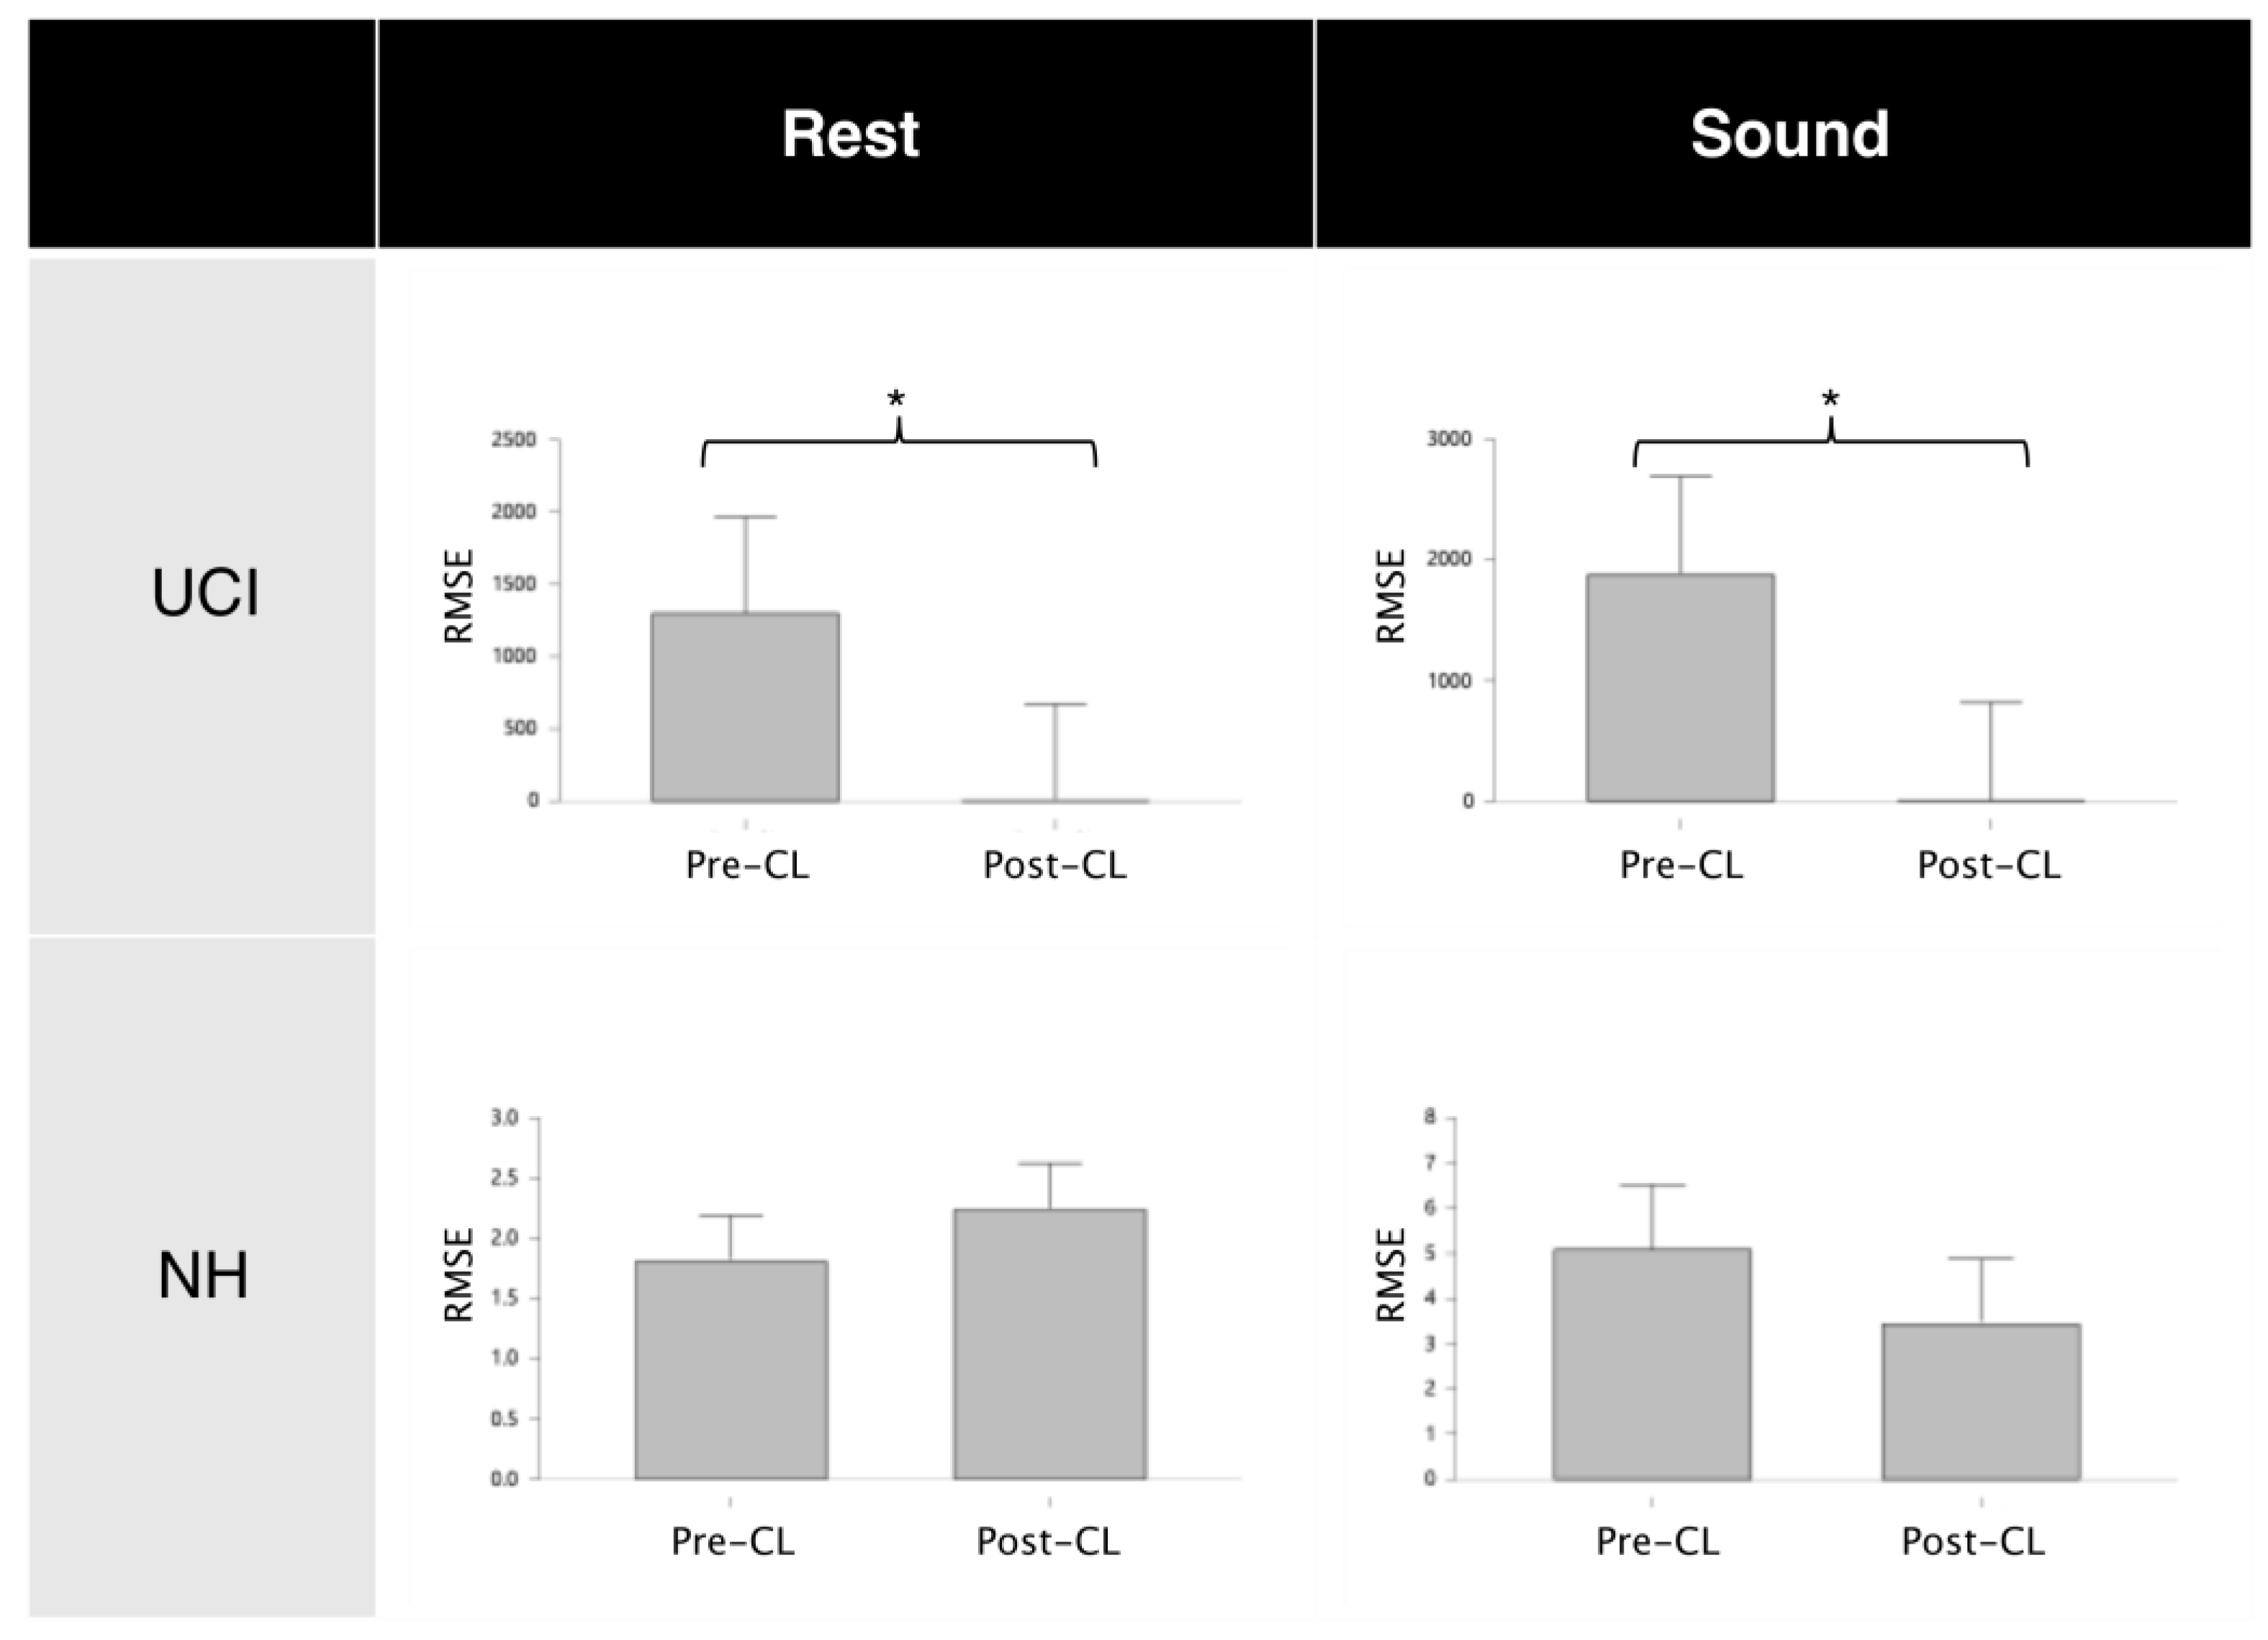

3.2. CI Artifact Reduction

3.3. Neurophysiological Results